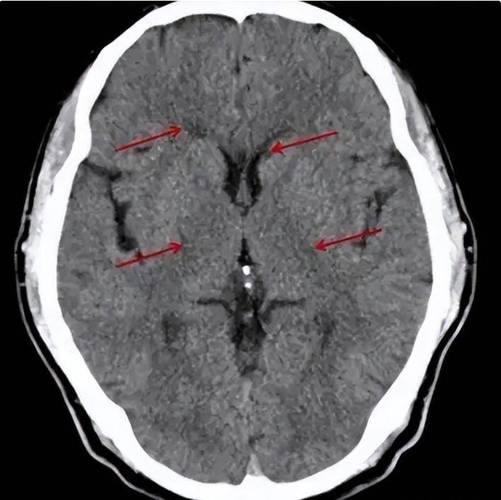

腔梗:

(图片来源网络,侵删)- 这是核心诊断。“腔隙性脑梗塞”的简称。

- 形成原因:我们的大脑里有非常细小的血管,叫做“穿通动脉”,这些血管为大脑深部的一些重要结构(如基底节、丘脑、脑干等)供血,当这些小血管因为各种原因(比如堵塞、变性)发生堵塞时,它所供应的那一小块脑组织就会因为缺血而坏死,形成一个微小的“洞”或“腔隙”,这个坏死区域就叫做“腔隙性脑梗塞”。

少许:

表明数量不多,通常是1-3个,或者更多但分散,这提示病情可能处于早期或相对较轻的阶段。